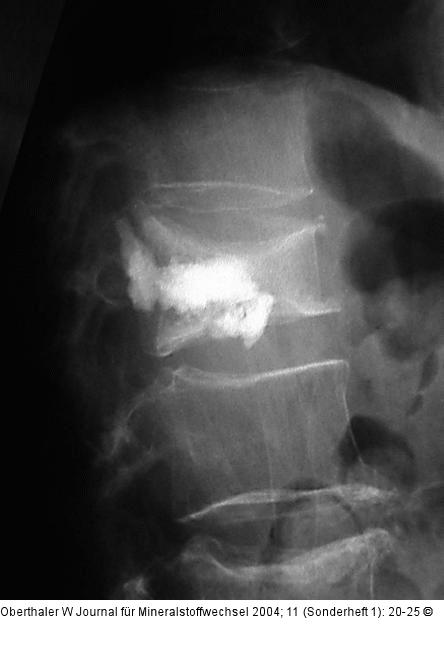

Abbildung 5: Kyphoplastie Ausflüsse von Zement in den Bandscheibenraum sind unproblematisch, nicht jedoch Austritte nach dorsal! |

Abbildung 5: Kyphoplastie

Ausflüsse von Zement in den Bandscheibenraum sind unproblematisch, nicht jedoch Austritte nach dorsal! |